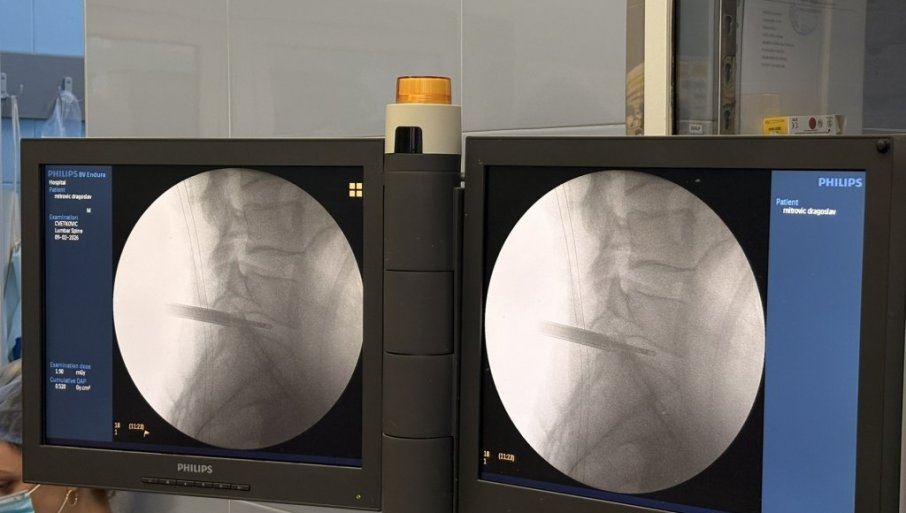

PRVA ENDOSKOPSKA OPERACIJA DISKUS HERNIJEU UKCV: Značajan iskorak u primeni savremenih minimalno invazivnih tehnika

U UNIVERZITETSKOM kliničkom centru Vojvodine uspešno je izvedena prva kompletno endoskopska operacija lumbalne diskus hernije.

Operaciju su izveli doc. dr Bojan Jelača i prof. dr Đula Đilvesi, čime je UKCV napravio značajan iskorak u primeni savremenih minimalno invazivnih tehnika u spinalnoj hirurgiji. Pacijent koji je 8. februara operisan ovom metodom, otpušten je kući već narednog dana, uz uredan postoperativni tok i preporuku za dalji rehabilitacioni tretman.

Diskus hernija predstavlja jedno od najčešćih oboljenja savremenog doba, koje u velikoj meri pogađa radno aktivnu populaciju i dovodi do hroničnog bola, smanjenog kvaliteta života i čestih odsustava sa posla. Suština endoskopske tehnike zasniva se na radu kroz radni kanal prečnika oko 8 mm, uz konstantnu endoskopsku vizuelizaciju i irigaciju.